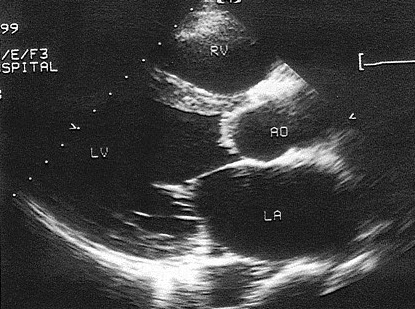

210、单项选择题

男28岁,胸部疼痛1周余,神清,心律齐,超声心动图如下,根据图片应提示()

D.三尖瓣下移

E.三尖瓣狭窄